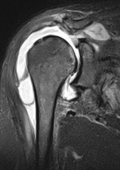

Meist handelt es sich bei Tumoren im Bereich des Stütz- und Bewegungsapparates um Metastasen (Tochtergeschwülste) anderer Krebserkrankungen. Aber auch primär können hier bösartige Geschwülste entstehen. Die Metastasierung in den Knochen ist häufig, wobei wiederum die Wirbelsäule im Vordergrund steht. Neben Schmerzen kann es zu einer Verminderung der Stabilität kommen, was zu Brüchen oder erhöhtem Risiko von Brüchen führt. Operative Maßnahmen haben neben der häufig radikalen Beseitigung des Tumorgewebes somit die Stabilisierung und Schmerzverminderung zum Ziel. Meisten ist ein interdisziplinäres Vorgehen mit anderen Fachrichtungen erforderlich, um folgende Strahlen- sowie Chemotherapien oder die Behandlung des zugrunde liegenden Krebsleidens zu koordinieren